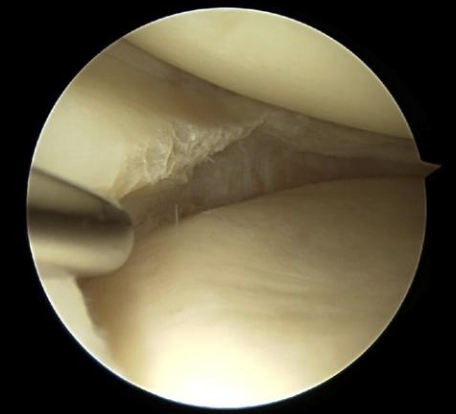

Illustraties van een meniscuscheur tijdens een kijkoperatie:

Flapscheur